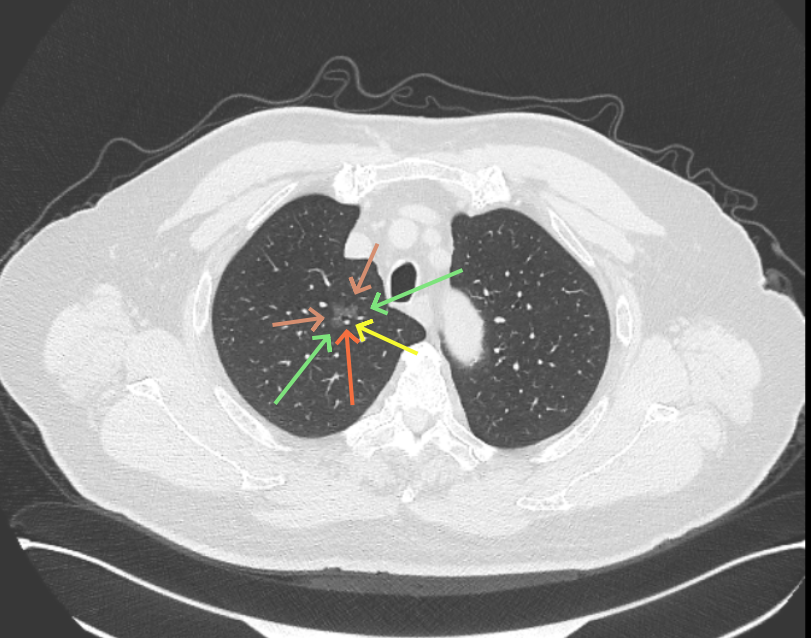

但病灶B却显然进展!变成以实性成分为主的了!

两处均有进展,混合密度这处更显著些。那要考虑手术了的。之前也有碰到较短时间内进展是伴炎症或纤维增生的,但我们不能赌。建议手术为宜。意见供参考!

再看2026年3月最近复查时不同层面病灶A的细节影像特征:

微小血管走向病灶,磨玻璃的密度淡而较纯。

再看病灶B的2026年3月细节影像特征:

边缘位置也是较淡的磨玻璃成分。

上图是混合密度,轮廓较清,瘤肺边界欠清晰。

病灶A以及他处磨玻璃结节其实进展都是不明显的,略与2022年比,病灶A稍显明显点。病灶B开始时极淡,之前进展虽有但也甚微,直到2025年9月仍是磨玻璃成分为主,只是点状少许密度稍高成分。但在最近半年内却显然进展!若从影像上判断,基本上就得是浸润性腺癌了。那有几点:一是必不能再随访;二是大小来看仍是1A期;三是从快速进展来说,可能含有部分高危亚型,比如微乳头或实体型等;四是他处的磨玻璃结节以及病灶A显然不能用病灶B的转移来解释,仍考虑是多原发早期肺癌。

结友问能否先穿刺?我是这么考虑的:你这个病灶B一是位置深,且靠近附近的血管,不容易穿刺;二是从影像变化来看,基本上肯定是恶性的,不是100%,也是95%以上的概率。刚才我又在重建看冠状位与矢状位以及各次影像,目前混合密度的其实是后来者居上,原来刚开始是它比旁边的病灶密度淡的,但它的密度不是太纯,前次你自己也说似乎有点状偏实性成分。只是最近这半年进展特别快。这说明它的恶性程度较它边上原来就比较明显的那处恶性程度高,亚型中大概率有低分化的成分。所以从目前的影像来看,要尽快手术,而且切肺叶更为稳妥些。

这是较为少见的一个病例,磨玻璃为主,而且一直瘤肺边界欠清晰的病灶何以会在之前三年均极缓慢微小变化的情况下,近半年却快速进展呢?从影像细节上看,我们能否进一步分析哪种纯磨玻璃结节可能会较快进展?结合本例,我个人的考虑是:1、病灶整体显得是磨玻璃密度,但灶内并不均匀,就如磨玻璃密度中混入细沙状;2、整体轮廓虽然较清但瘤肺边界相对来说却并不太清晰;3、邻近有血管紧挨,而且与病灶这间缺乏间隙;4、病灶密度不高,没有明显实性成分,却有灶内有细支气管通气征,说明肿瘤成分具有收缩力,却与纯磨的收缩不匹配(纯磨一般不太会有明显收缩力)。如果有上面这些特征可能要提高警惕,一是适当较短的随访间隔,二是影像细节变化要更加注意,开始变化意味着已经进入发展期,而非蛰伏期。当然是否在2025年9月时定得手术了?如果是孤立性的病灶B,且位置位于能简单楔形切除的位置,那是可以考虑的。但位置深、两肺多发,切除范围不小,再今年据肺癌诊疗指南中说的混合磨玻璃结节实性成分不足25%是非侵袭性病变,且几乎不会转移,那么按原则仍再随访显然是可以的。本例的随访变化再次表明磨玻璃密度肺癌的诊疗个体化之路仍是很漫长的,按指南原则的随访或诊疗显然不足以覆盖所有病例,总结与经验积累永远在路上。